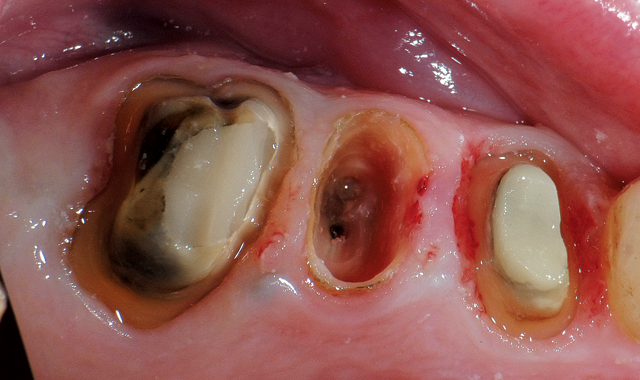

Fig. 2

Step 2: The crown was removed from tooth #13 and the tooth root was reduced approximately 5 mm apical from the crest of the ridge, leaving a thin wall of tooth root (Fig. 2). This technique simulates the socket without any bleeding. Images can easily be taken with the CEREC Omnicam.